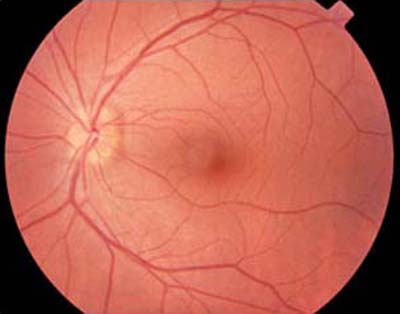

¿Por qué se considera un problema grave un desgarro en la Retina?

Cuando se produce un desgarro en la retina, el líquido situado en la cavidad vítrea puede pasar a través del desgarro y situarse bajo la retina; poco a poco, el líquido del vítreo pasa a través del desgarro retiniano y se instala debajo de la retina, separándola de la pared posterior del ojo. Esta separación, se denomina desprendimiento de retina y la visión se pierde en el lugar en que la retina se desprende.

Puesto que la mayoría de desgarros se localizan en la retina periférica (o parte lateral de la Retina), el desprendimiento produce en primer lugar pérdida de la visión lateral o periférica. Un paciente puede apreciar una sombra oscura o un velo que procede de un lado, de arriba o de abajo. En la mayoría de los casos, después del comienzo de un desprendimiento, toda la retina se desprenderá finalmente y se perderá toda la visión útil de ese ojo.

Diagrama Desprendimiento de Retina

Retinografía, Desprendimiento de Retina